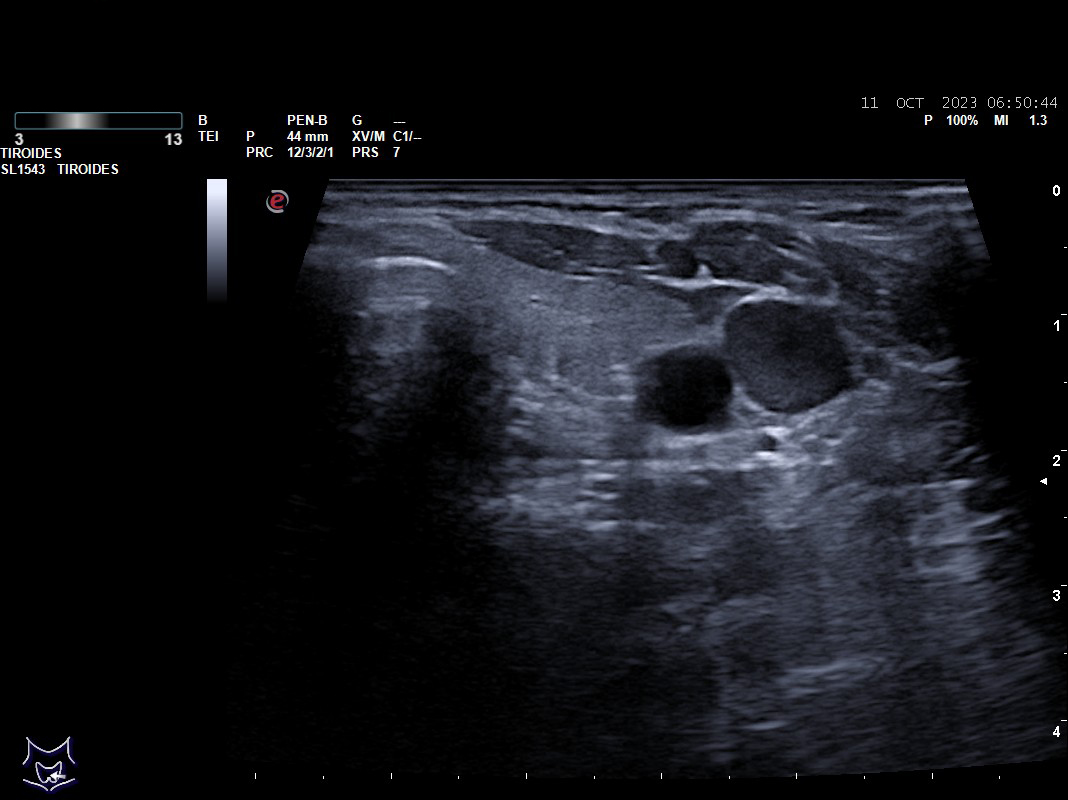

Hallazgos ecográficos: nódulos tiroideos subcentimétricos sin cambios, yugular interna izda con contenido discretamente hiperecogénico que no capta Doppler y colapsabilidad incompleta.

Se deriva a urgencias es valorada por cirugía vascular quienes describen la presencia del trombo sin poder precisar su final y se ingresa a la paciente ya que el servicio de radiología no considera realizar en ese momento el estudio pertinente.

Tras cinco días de ingreso se realiza un ecodoppler reglado descartándose la trombosis venosa, se suspende la anticoagulación y se da de alta sin tratamiento.